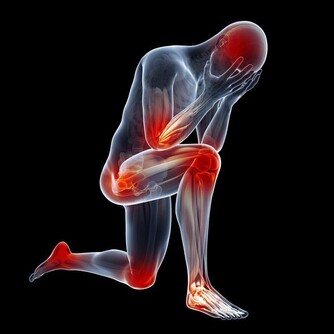

2、 及時治療誘發病

大部分患上中風的人一般都有如下特徵:身材肥胖,血壓高,患有多種心腦血管疾病,最常見的就是冠心病,動脈硬化,糖尿病。從根本上就要把血壓穩定在一個固定值,不能使血壓一直上升,除此之外,還要及時的治療這些心腦血管疾病,即使已經是無法治癒的話,也要穩住病情不能讓其繼續嚴重下去。堅持去測量血壓,長期堅持不降壓藥。